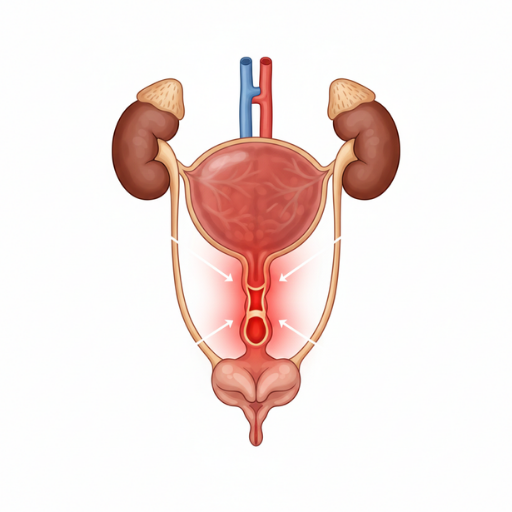

Narrow Urethra is a condition in which the urinary passage becomes constricted, leading to weak urine flow, straining during urination, burning sensation, or incomplete bladder emptying. Early diagnosis and proper management help restore smoother urine flow and prevent complications such as recurrent infections or urinary retention.

Narrow urethra refers to a condition in which the urinary passage becomes constricted, leading to difficulty in the normal flow of urine. This narrowing may develop due to inflammation, minor injury, infection, irritation, or early scar tissue formation. Patients commonly experience a weak or thin urine stream, difficulty starting urination, straining while passing urine, prolonged urination time, spraying of urine, or a sensation of incomplete bladder emptying. In some cases, burning during urination or increased frequency may also occur. Early identification of these symptoms helps prevent progression and complications.

Narrow urethra, a condition in which the urinary passage becomes constricted and causes difficulty in urine flow, can lead to symptoms such as weak or thin urine stream, straining during urination, burning sensation, spraying of urine, prolonged urination time, or recurrent urinary discomfort. Early management is important to prevent progression and avoid complications like infections or urinary retention.

Patients with a narrow urethra may experience symptoms related to partial obstruction of urine flow. Common signs include a weak or thin urine stream, difficulty starting urination (hesitancy), prolonged time to pass urine, and the need to strain while urinating. Some individuals may also notice a split or spraying urine stream due to narrowing at the urinary passage.

Additional symptoms can include mild burning sensation during urination, increased frequency of urination, dribbling after urination, and a feeling that the bladder is not completely empty. In certain cases, recurrent urinary discomfort or infections may occur if the narrowing persists.

If left untreated, significant narrowing can sometimes progress to severe obstruction or urinary retention, requiring prompt medical care. Early recognition of these symptoms is important for proper evaluation and timely management, helping maintain healthy and comfortable urinary function.